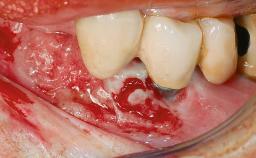

A 82-year-old female patient was referred to the Department of Oral Surgery and Stomatology at the University of Bern, Switzerland, for further diagnosis and treatment of growing discomfort in the right mandible (implant 45) and left maxilla (implant 23). The patient had had implants of various types inserted in the mandible and maxilla over the course of the previous three decades (in the 1980s and 1990s). The patient had received removable partial dentures on implants in the maxilla and on natural teeth in the mandible. The implants in the posterior right mandible had been restored with two splinted single crowns. The lower partial denture was not well tolerated by the patient and therefore had not been worn for over ten years. After insertion of the implants, there had been no complications for many years, but implants 45 and 46 as well as 23 had begun to exhibit signs of peri-implantitis with limited bone loss several years previously. The infection had been treated by the private practitioner, and bone loss around the three implants had not progressed until about half a year previously.